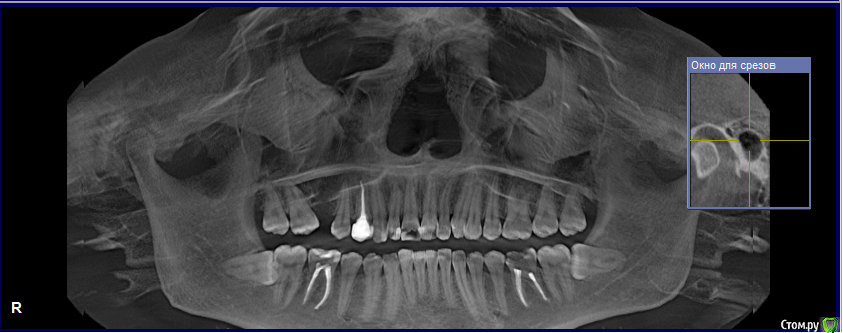

Naliy Опубликовано 2 июля, 2020 Поделиться Опубликовано 2 июля, 2020 Добрый день!Мне 24 года. Два года назад из-за неправильного лечения и пломбирования пришлось удалить шестой зуб сверху (правая сторона). В настоящее время началась рецессия десны на верхнем левом клыке, и стоматолог полагает, что это связано с неравномерной нагрузкой на челюсть из-за отсутствия зуба, поэтому советует ортодонтическое лечение.За 2 года 7 и 8 зубы сдвинулись и оставили 4-5 мм от пустого места 6 зуба. Прикус дистальный; по словам одного ортодонта, зубы с правой стороны смыкаются более-менее правильно, а с левой - нет. На зубах есть меловидные пятна, есть пломбы.Побывала у трех ортодонтов, но мнения у них расходятся немного:1) удалить зубы мудрости, освободить место под имплант;2) удалить один зуб мудрости с верхней челюсти, передвинуть 7 и 8;3) удалить один зуб мудрости и один 4 зуб слева и сдвинуть 7 - 8. Имплантолог сказал, что кость в районе 6 зуба тонкая, а ортодонтическое лечение неизбежно,т.к. мало места для импланта. Подскажите, как лучше решить проблему отсутствующего зуба?1. Можно ли передвинуть 7 и 8 на место 6? Высока ли вероятность неудачного исхода? 2. Необходимо ли удалять 4 зуб для выравнивания зубного ряда? Врач может определить необходимость удаления зуба только с помощью специальных расчетов или КТ и очного осмотра достаточно?3. Обязательно ли носить брекеты на нижней челюсти? Можно ли попробовать их выпрямить трейнерами, т.к. полноценное лечение очень трудно в финансовом плане. Поэтому я надеюсь или на лечение на обеих челюстях с передвижением 7-8 зубов, или на лечение верхней челюсти с последующей имплантацией. Буду благодарна за вашу помощь. Ссылка на комментарий

Дмитрий Л. Опубликовано 3 июля, 2020 Поделиться Опубликовано 3 июля, 2020 Нужно комплексное ортодонтическое лечение. Удалить верхнюю 8, отодвинуть 7 и поставить имплант в позицию 6. Трейнеры неэффективны. Рецессия на левом клыке с отсутствующим зубом не связана. Побывала у трех ортодонтов, но мнения у них расходятся немного:1) удалить зубы мудрости, освободить место под имплант;2) удалить один зуб мудрости с верхней челюсти, передвинуть 7 и 8;3) удалить один зуб мудрости и один 4 зуб слева и сдвинуть 7 - 8.Видимо вы запутались немного и неправильно поняли докторов. Ссылка на комментарий

Naliy Опубликовано 3 июля, 2020 Автор Поделиться Опубликовано 3 июля, 2020 Дмитрий, спасибо, что откликнулись на тему!Я не очень понимаю, почему Вам кажется, что я неверно восприняла слова докторов. Пишу чуть подробнее их ответы:1. Удалить оба зуба мудрости с верхней челюсти, передвинуть назад седьмой зуб и освободить место под имплант.2. Удалить один зуб мудрости (с левой стороны), а правый зуб мудрости и седьмой передвинуть на место удаленного.3. Удалить один зуб мудрости (с левой стороны) и четвертый зуб (с левой стороны), чтобы было пространство для выравнивания зубного ряда и освободить место для второго левого зуба; передвинуть правый зуб мудрости и семерку на место удаленного. Подскажите, почему по Вашему мнению нужно делать именно имплантацию, а не передвижение зубов? Вы не могли бы подсказать к какому специалисту нужно обратиться для выявления причины рецессии и ее устранения? Полное ортодонтическое лечение я не могу себе позволить из-за высокой стоимости, поэтому не могу рассматривать вариант брекетов на две челюсти и последующей имплантации, плюс судя по словам имплантолога возможно понадобиться восстановление костной ткани. Ссылка на комментарий